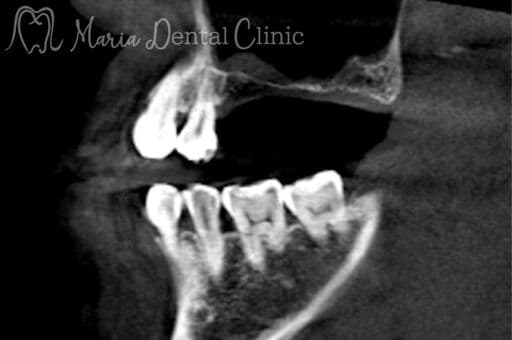

サイナスリフトの症例

【症例】サイナスリフトで骨を増やし、奥歯の支えを回復したインプラント治療

本症例の患者様は、右側の歯を抜歯した後そのまま放置していたことで噛み合わせが大きく乱れ、右上の歯周病が進行して抜歯に至りました。抜歯後は上顎洞に近接して骨量が著しく不足していたため、サイナスリフトによって新たな骨を増やし、インプラントを支える土台を再建しました。十分な骨量を確保することで、奥歯の咬合支持を回復した症例です。

before

after

治療内容 サイナスリフト、インプラント、矯正治療

治療期間 10ヶ月

治療回数 4回(他、抜糸、術後3ヶ月後、1年後の経過観察等を除く)

治療費用 3,300,000円(税込、サイナスリフト他、矯正治療を含む)

症例から言えること

本症例は、抜歯後の欠損部を放置すると歯が傾斜し、咬合支持が失われることで噛み合わせ全体が乱れ、別の部位の歯周病が急速に悪化することを示しています。さらに、こうした連鎖は将来的な大きな咬合崩壊につながる可能性があります。一方、骨量不足があってもサイナスリフトによりインプラントを支える骨を再建することで、機能を回復し、咬合の安定を取り戻すことが可能です。複雑な症例ほど、早期の診査・診断と適切な処置が咬合崩壊を防ぐ鍵となります。